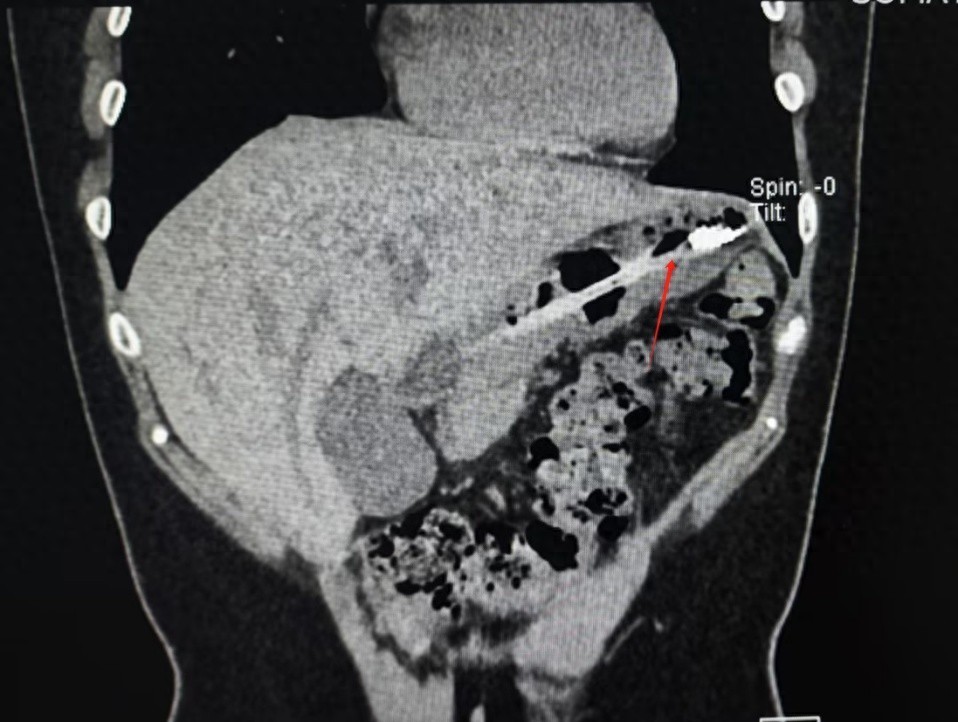

近日,游客小李(化名)到成都旅游,每天几顿不重样的体验成都美食。结果,因为反复的暴饮暴食,小李感觉胃胀、胃痛、反酸、打嗝,出现了明显消化不良的表现,同时大量进食也让她产生了深深的身材焦虑。随后小李选择了催吐来缓解胃不适和长胖焦虑。为效果更好,该女子用一次性牙刷作为工具,结果手打滑,18cm长牙刷顺着咽喉直接滑了下去。幸运的是,由于女子就医及时,在医生的帮助下牙刷顺利取出,并未对胃壁造成严重的损伤。医生表示,牙刷这种异物掉入胃中并不常见,而且牙刷的硬度和形状可能会对胃壁造成划伤、穿孔等损伤,还好患者来得及时,如果牙刷继续掉入肠道,还可能引起肠梗阻等严重后果。图:胃中取出的牙刷网友惊呆:那也不能催吐吧?维尼:少吃点不就对了吗?又节约钱,对身体又好,重点还不长胖。搜罗超可爱:她这不是想轻轻吐一点,是想吐干净,好可怕。戒酒撒娇:这种心态我懂,猪瘾发作后又后悔,但是催吐真的很伤身体。养乐多跑:把一次性牙刷当作催吐工具,这…催吐的代价,到底有多沉重?当下,有不少人受到网络上不良信息的影响,以瘦为美,为了减肥常错误、滥用催吐。此前媒体曾报道过,在电商平台上,半米长的聚氯乙烯软管,被称作“仙女管”、“兔兔管”。卖家表示需要将催吐管插进胃里50cm,使食物顺着管子吐出来,平均1个月可瘦超过5公斤且使用无异物感,相对手动催吐无副作用,但当记者询问有无相关检验资质证明时,商家表示无法提供。事实上,催吐对人体的身心健康危害极大:进食障碍诊治专家陈珏教授称,催吐行为对健康存在重大危害,会损伤食道、牙齿、腮腺、唾液腺、胰腺等部位,造成体内电解质紊乱、心率失常,出现抽搐、休克、癫痫发作等严重后果,甚至心脏骤停导致死亡。另外,据复旦大学附属儿科医院心理科表示:催吐严重者会引起心理扭曲,因为滥用催吐而患厌食症,丧失生活自理和工作能力。例如,美国模特Jeremy Gillitzer,因为职业要求不得不控制饮食,但是自己又压抑不了食欲,于是就选择了催吐的方式。渐渐,他的身体承受不了折腾,患上了厌食症,年仅38岁去世,当时体重只有39公斤。来源: 第一现场&壹深圳